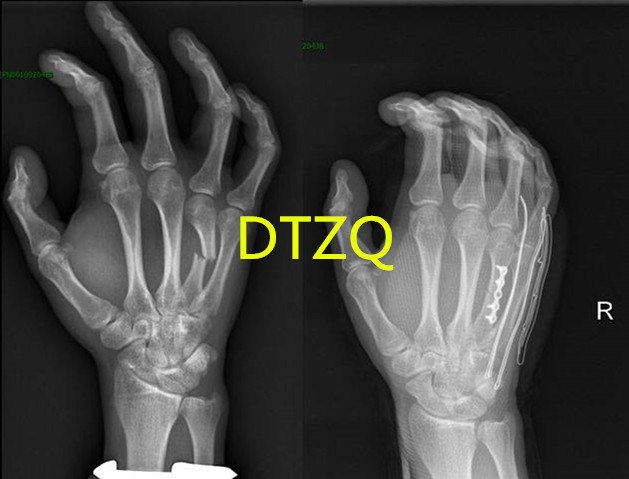

年轻人掌骨骨折手术治疗可以早期功能锻炼

629x479 - 47KB - JPEG